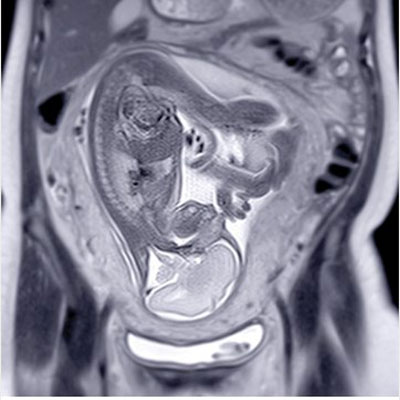

دوره UCSF ObGyn Women’s Imaging 2025 یکی از معتبرترین برنامههای آموزشی در زمینه تصویربرداری زنان و زایمان است که توسط دانشگاه UCSF و جمعی از اساتید برجسته رادیولوژی برگزار شده است. این مجموعه شامل ویدیوهای آموزشی با کیفیت بالا و فایلهای PDF اسلایدها میباشد و آخرین پیشرفتها در تصویربرداری پیش از تولد، سونوگرافی، MRI و ماموگرافی را پوشش میدهد.

تصویربرداری در بارداریهای پرخطر و بررسی جنین

MRI لگن و کاربردهای آن در بیماریهای زنان

تفسیر یافتههای سونوگرافی در ارزیابی تخمدان، رحم و لگن